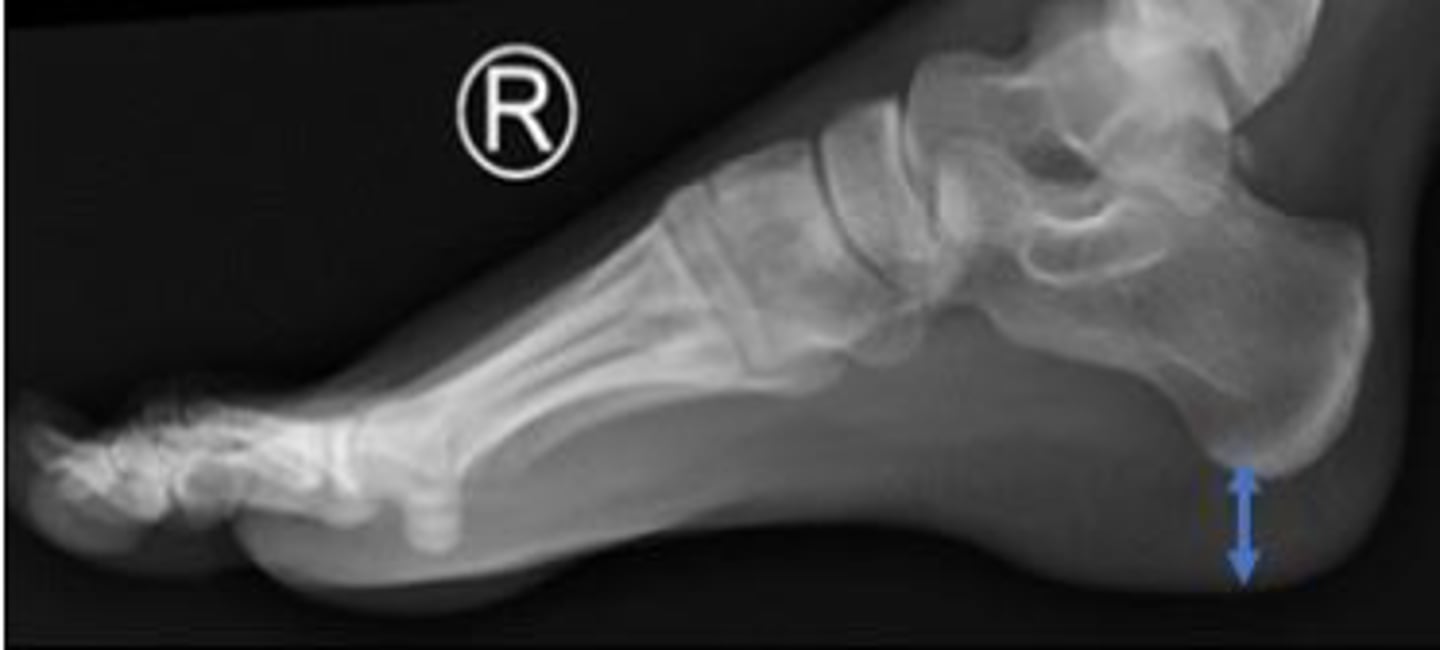

Right lateral foot

What is the name of the radiographic view?

Heel pad of the right foot

What are the arrows pointing to?

Head of the talus of the right foot

Calcaneus of the right foot

Navicular of the right foo

What is outlined?

Medial malleolus of the right foot

What is the arrow pointing to?

Heel pad measurement

What is the name of the assessment?

Females: average 19mm (maximum of 23mm)

Males: average 19mm (maximum of 25mm)

What is the normal range for the assessment?